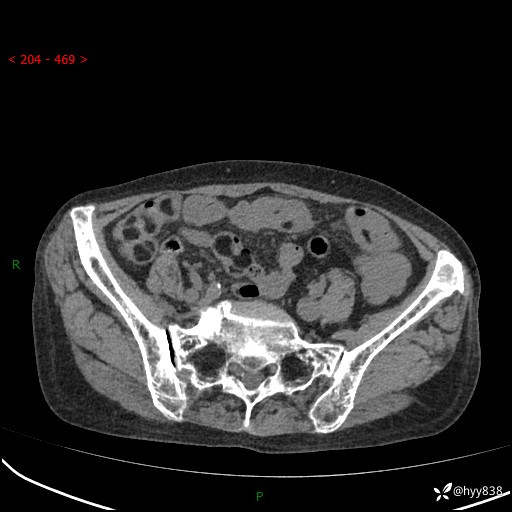

全腹部CT平扫